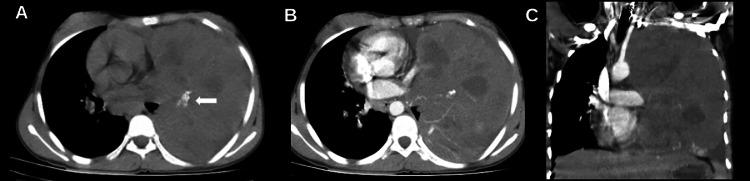

Primary pleuropulmonary synovial sarcoma (PPSS) is a rare malignant soft tissue sarcoma primarily affecting adolescents and young adults. Diagnosis relies on clinical examination, radiological imaging, and confirmation through histopathological and immunohistochemical analyses. Due to nonspecific symptoms, diagnosis is often delayed. Treatment typically involves a multimodal approach, including systemic chemotherapy, surgical intervention, and radiotherapy. We present the case of a 14-year-old female with a 5-month history of cough, low-grade fever, and weight loss. A contrast-enhanced chest CT scan revealed a large left thoracic mass with lung infiltration, mediastinal invasion, and multiple enlarged lymph nodes. Histopathological and immunohistochemical analyses confirmed a primary pulmonary synovial sarcoma positive for transducer-like enhancer of split-1 (TLE-1). The patient underwent 2 cycles of neoadjuvant chemotherapy with ifosfamide and doxorubicin, but no significant improvement was observed. Local control options, including surgery and radiotherapy, were deemed infeasible, and palliative care was initiated.

原发性胸膜肺滑膜肉瘤(PPSS)是一种罕见的恶性软组织肉瘤,主要影响青少年和年轻成年人。诊断依赖于临床检查、影像学检查,并通过组织病理学和免疫组织化学分析来确诊。由于症状不具特异性,诊断往往会延迟。治疗通常采用多模式方法,包括全身化疗、手术干预和放疗。我们报告一例14岁女性患者,有5个月的咳嗽、低热和体重减轻病史。增强胸部CT扫描显示左胸有一个大肿块,伴有肺部浸润、纵隔侵犯和多个肿大淋巴结。组织病理学和免疫组织化学分析证实为原发性肺滑膜肉瘤,对分裂样增强子-1(TLE-1)呈阳性。该患者接受了2个周期的异环磷酰胺和阿霉素新辅助化疗,但未见明显改善。包括手术和放疗在内的局部控制方案被认为不可行,于是开始了姑息治疗。